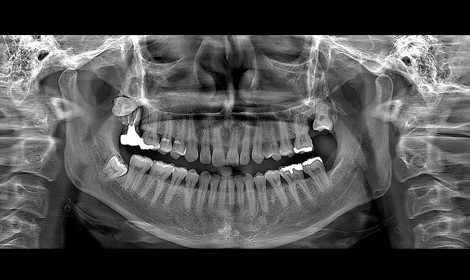

Pantomogram jest zdjęciem przeglądowym, które przedstawia ogólny stan wszystkich zębów. Oprócz oceny stanu uzębienia, umożliwia także zobrazowanie struktur anatomicznie przyległych takich jak kości szczęki i żuchwy, stawy skroniowo-żuchwowe i częściowo zatoki szczękowe. Pantomogram powinien być wykonywany rutynowo, raz na jakiś czas w celu kontroli stanu narządu żucia.

Wychodząc naprzeciw oczekiwaniom współczesnego pacjenta, stworzyliśmy nowoczesne i w pełni wyposażone centrum cyfrowej diagnostyki RTG i tomografii komputerowej 3D. W celu zapewnienia najwyższych standardów diagnostycznych oddajemy do Państwa dyspozycji jeden z najnowocześniejszych aparatów tomograficznych 3D, obecnych na rynku.